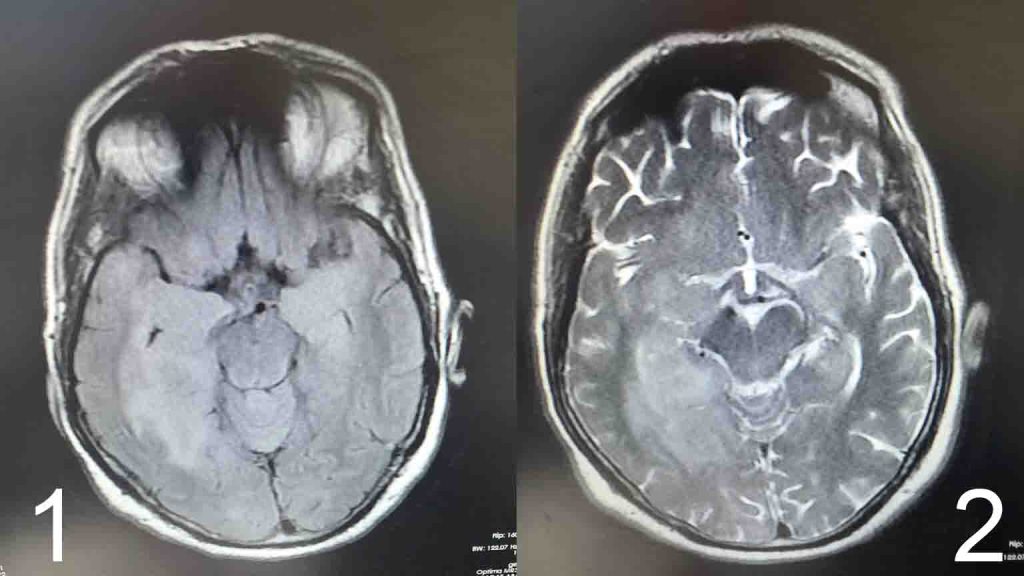

علائم بیماری سیر پیشرونده داشته و سپس دچار اختلالات شدید رفتاری، بی قراری و شخصیتی واضح می شوند.برای بیمار ام ار آی مغز در خواست می شود که ضایعات هیپرسیگنال وسیع در لوب تمپورال و فرونتال رویت می شود. ( تصویر ۱ و ۲ )

در ام ار ای مجدد، ضایعات دوطرفه لوب های تمپورال و فرونتال دیده شد.

۲. در ام ار آی مغزی، ضایعات دو طرفه لوب های تمپورال و فرونتال داشت.